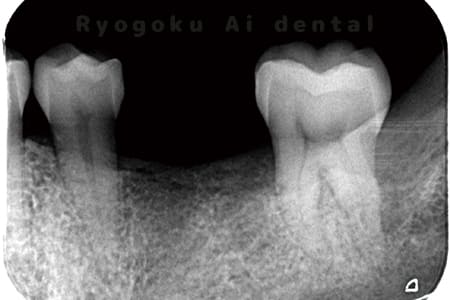

Case03

- 原因

- 急性化膿性根尖性歯周炎

- 治療期間

- 2ヶ月

- 治療内容

- マイクロエンド

- 治療費用

- 121,000円

黙っていても痛みが出るとのことで来院した患者様です。本治療は症状もあるため、抜髄治療をマイクロエンドで行いました。

<リスク・副作用>

術後は痛み、腫れ、痺れなどの副作用が生じる場合があります。症状が再発する可能性があります。